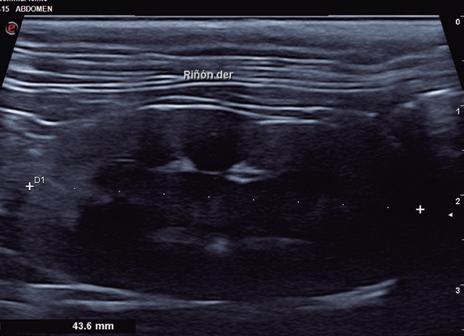

La ecografía es parte importante de los procedimientos de diagnóstico al servir para explorar la mayoría de los órganos del cuerpo. Las ondas ultrasónicas se emplean sobre todo para realizar la ecografía abdominal y la ecocardiografía. En la ecografía abdominal se explora la región abdominal junto con las venas y los ganglios linfáticos, y permite valorar alteraciones del hígado, los riñones, páncreas, y el útero, entre otros órganos. En la ecocardiografía se exploran el corazón, el pericardio y los vasos sanguíneos que llegan al corazón o salen de él.